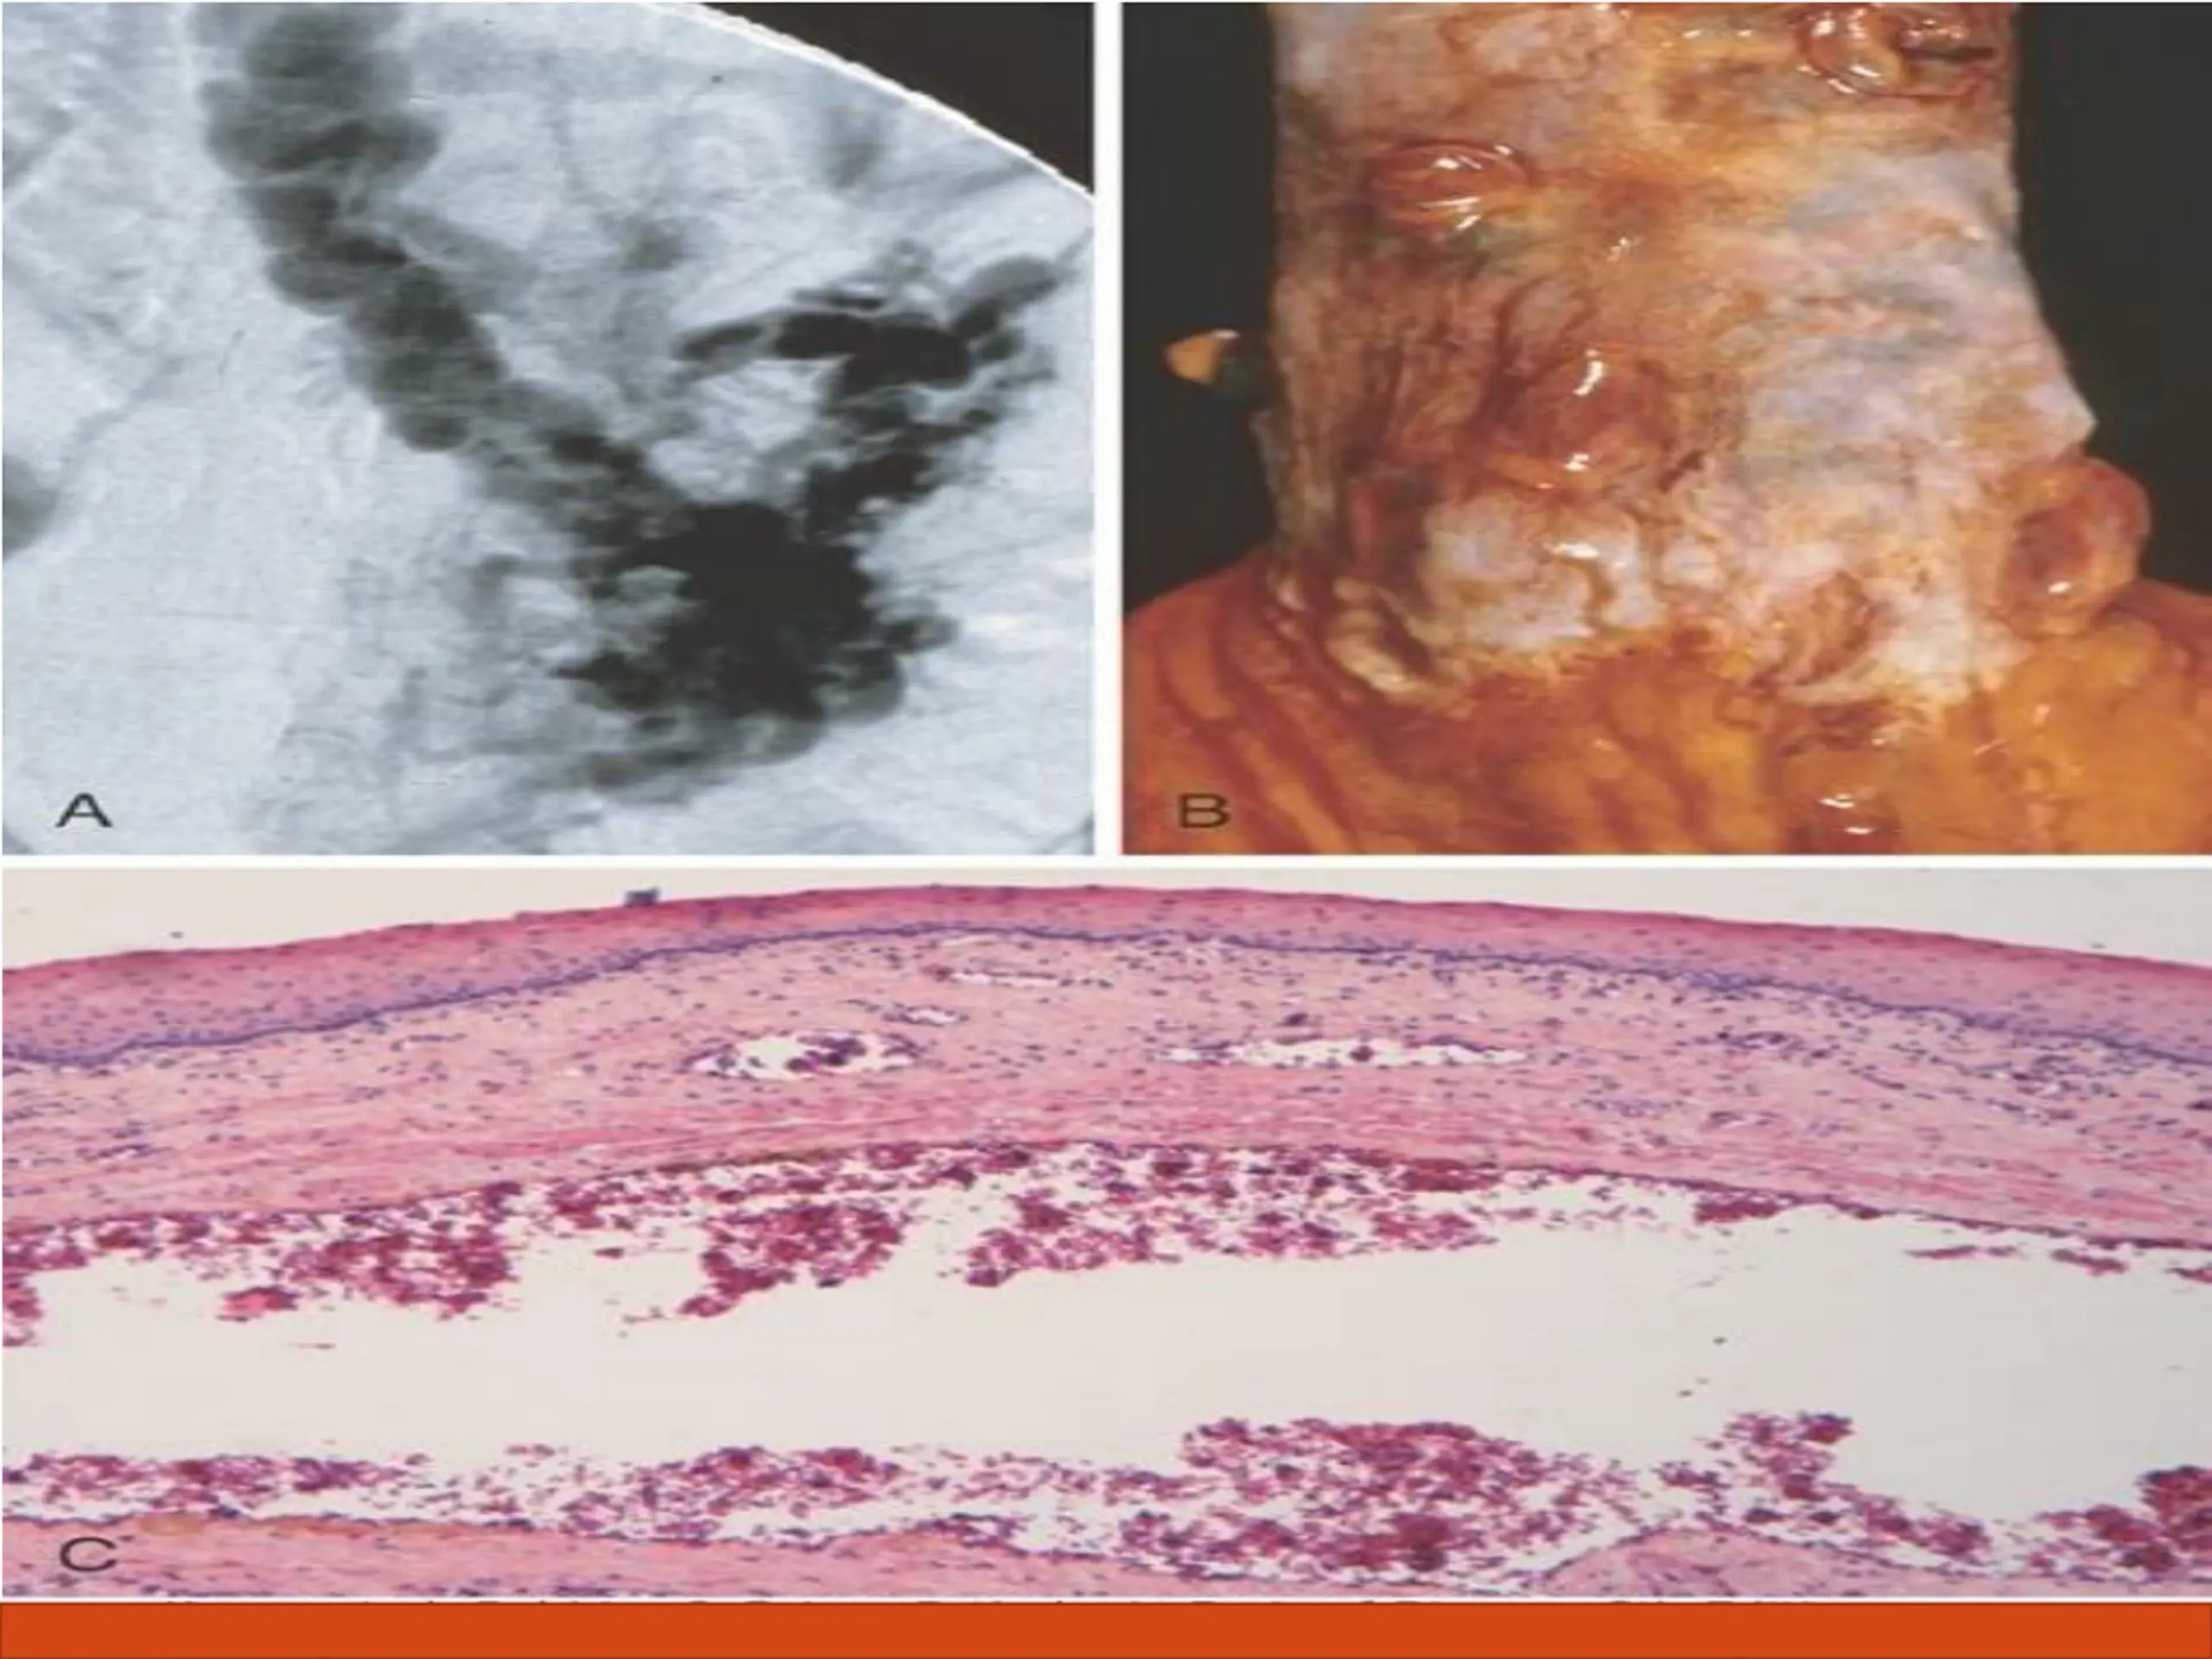

Complications of liver cirrhosis Morphology. Varices can be detected by venogram : tortuous dilated veins lying primarily within the submucosa of the distal esophagus and proximal stomach. Venous channels directly beneath the esophageal epithelium may also become massively dilated. Varices may not be grossly obvious in surgical or postmortem specimens, because they collapse in the absence of blood flow . Variceal rupture results in hemorrhage into the lumen or esophageal wall, in which case the overlying mucosa appears ulcerated and necrotic. If rupture has occurred in the past, venous thrombosis, inflammation, and evidence of prior therapy may also be present.